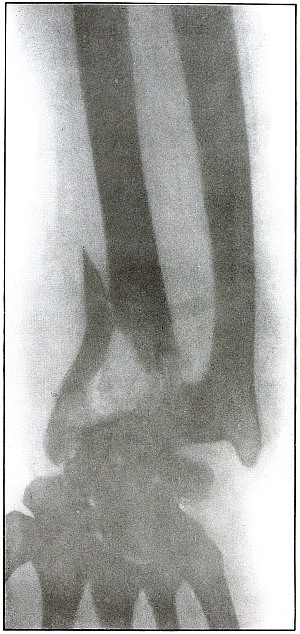

Plate 61.

_

[Pg 133]

Rifle—Plate 61.

LOWER EXTREMITY.

Gunshot Fracture of the Lower Ends of the Tibia and Fibula.

The course of the bullet was transverse, with the velocity of mid-range.

The fragmentation of the fibula, lying close to the skin, would produce considerable laceration in the wound of exit.

The treatment is conservative. Infection would depend almost entirely upon the integrity of the first dressings and immobilization.

Results should be favorable, with care in subsequent treatment. [Pg 134]